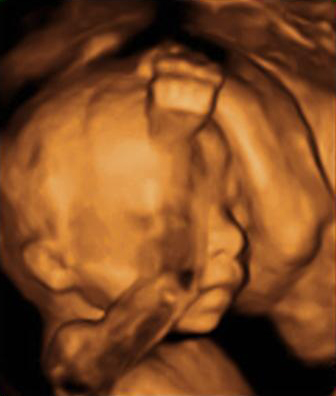

Las ecografías en 4D realizadas en la semana 20 de embarazo permiten ver el sexo femenino del feto con nitidez. En este caso, se ha capturado la imagen de los genitales femeninos, en concreto, la vulva.

Ecografía: Genitales de una niña de 20 semanas

En este ultrasonido, podemos ver la vulva del feto y otros pequeños detalles del sexo fetal.